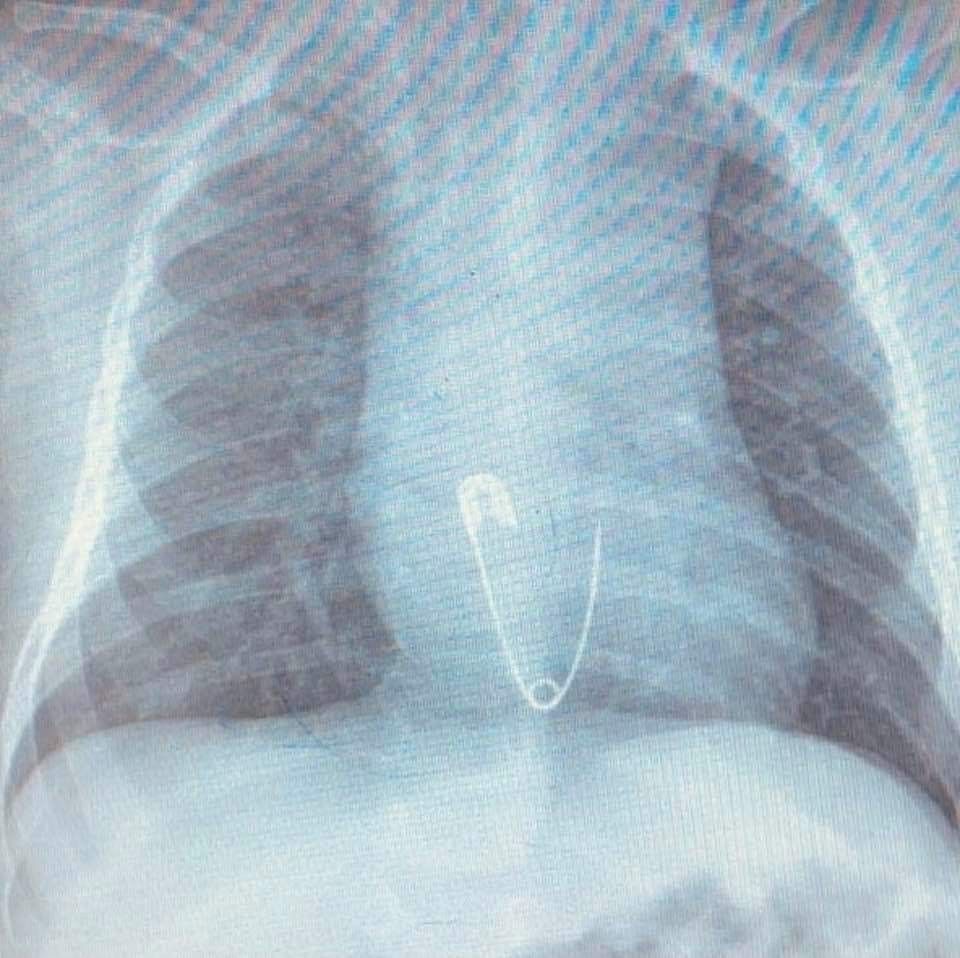

Yuttuğu çengelli iğne yemek borusuna saplanan 5 aylık bebek, Diyarbakır'dan Elazığ'a sevk edildi. Yapılan operasyonla iğne çıkarıldı.

Diyarbakır'da ikamet eden Esvet ile Amine Solmaz çiftinin tek çocukları olan 5 aylık Efraim'in nefes borusuna ailenin taktığı çengelli iğneli nazar boncuğu kaçtı. Aile bebeklerinin ağzına kaçan nazar boncuğunu çıkardı ama çengelli iğneyi çıkaramayınca en yakın hastaneye başvurdu. Burada yapılan ilk müdahalenin ardından bebek Elazığ'a sevk edildi. Ambulansla Fırat Üniversitesi (FÜ) Hastanesi Çocuk Gastroenteroloji Hepatoloji ve Beslenme Bölümü'ne getirilen bebeğin yapılan tetkiklerinde iğnenin yemek borusunun alt kısmında takılı kaldığı tespit edildi. Hemen Çocuk Endoskopi Ünitesine alınan bebeğin nefes borusundaki iğne, yapılan endoskopik yöntemle yaklaşık 15 dakikalık sürede çıkarıldı. Sağlık durumu iyi olan bebek ve ailesi taburcu edildi.

Hastanın Diyarbakır'dan Elazığ'a geldiğini belirten Prof. Dr. Yaşar Doğan, Hastayı kabul ettik, 5 aylık bir hasta. Bize gelmeden önce üzerinde bulunan nazar boncuğunu çengelli iğne ile birlikte ağzına götürmüş. Aile de fark edince müdahale etmiş, ağzındaki nazar boncuğunu çıkarmış fakat o esnada çengelli iğne yemek borusuna kaçmış. Hasta geldiği zaman çektiğimiz röntgende çengelli iğne yemek borusunun alt kısmında takılı vaziyetteydi. Hastaya 15 dakikalık sedasyon altında işlem yapıldı, endoskopi ile parça çıkarıldı. Hasta şu anda gayet iyi. Biraz sonra da evlerine göndereceğiz dedi.